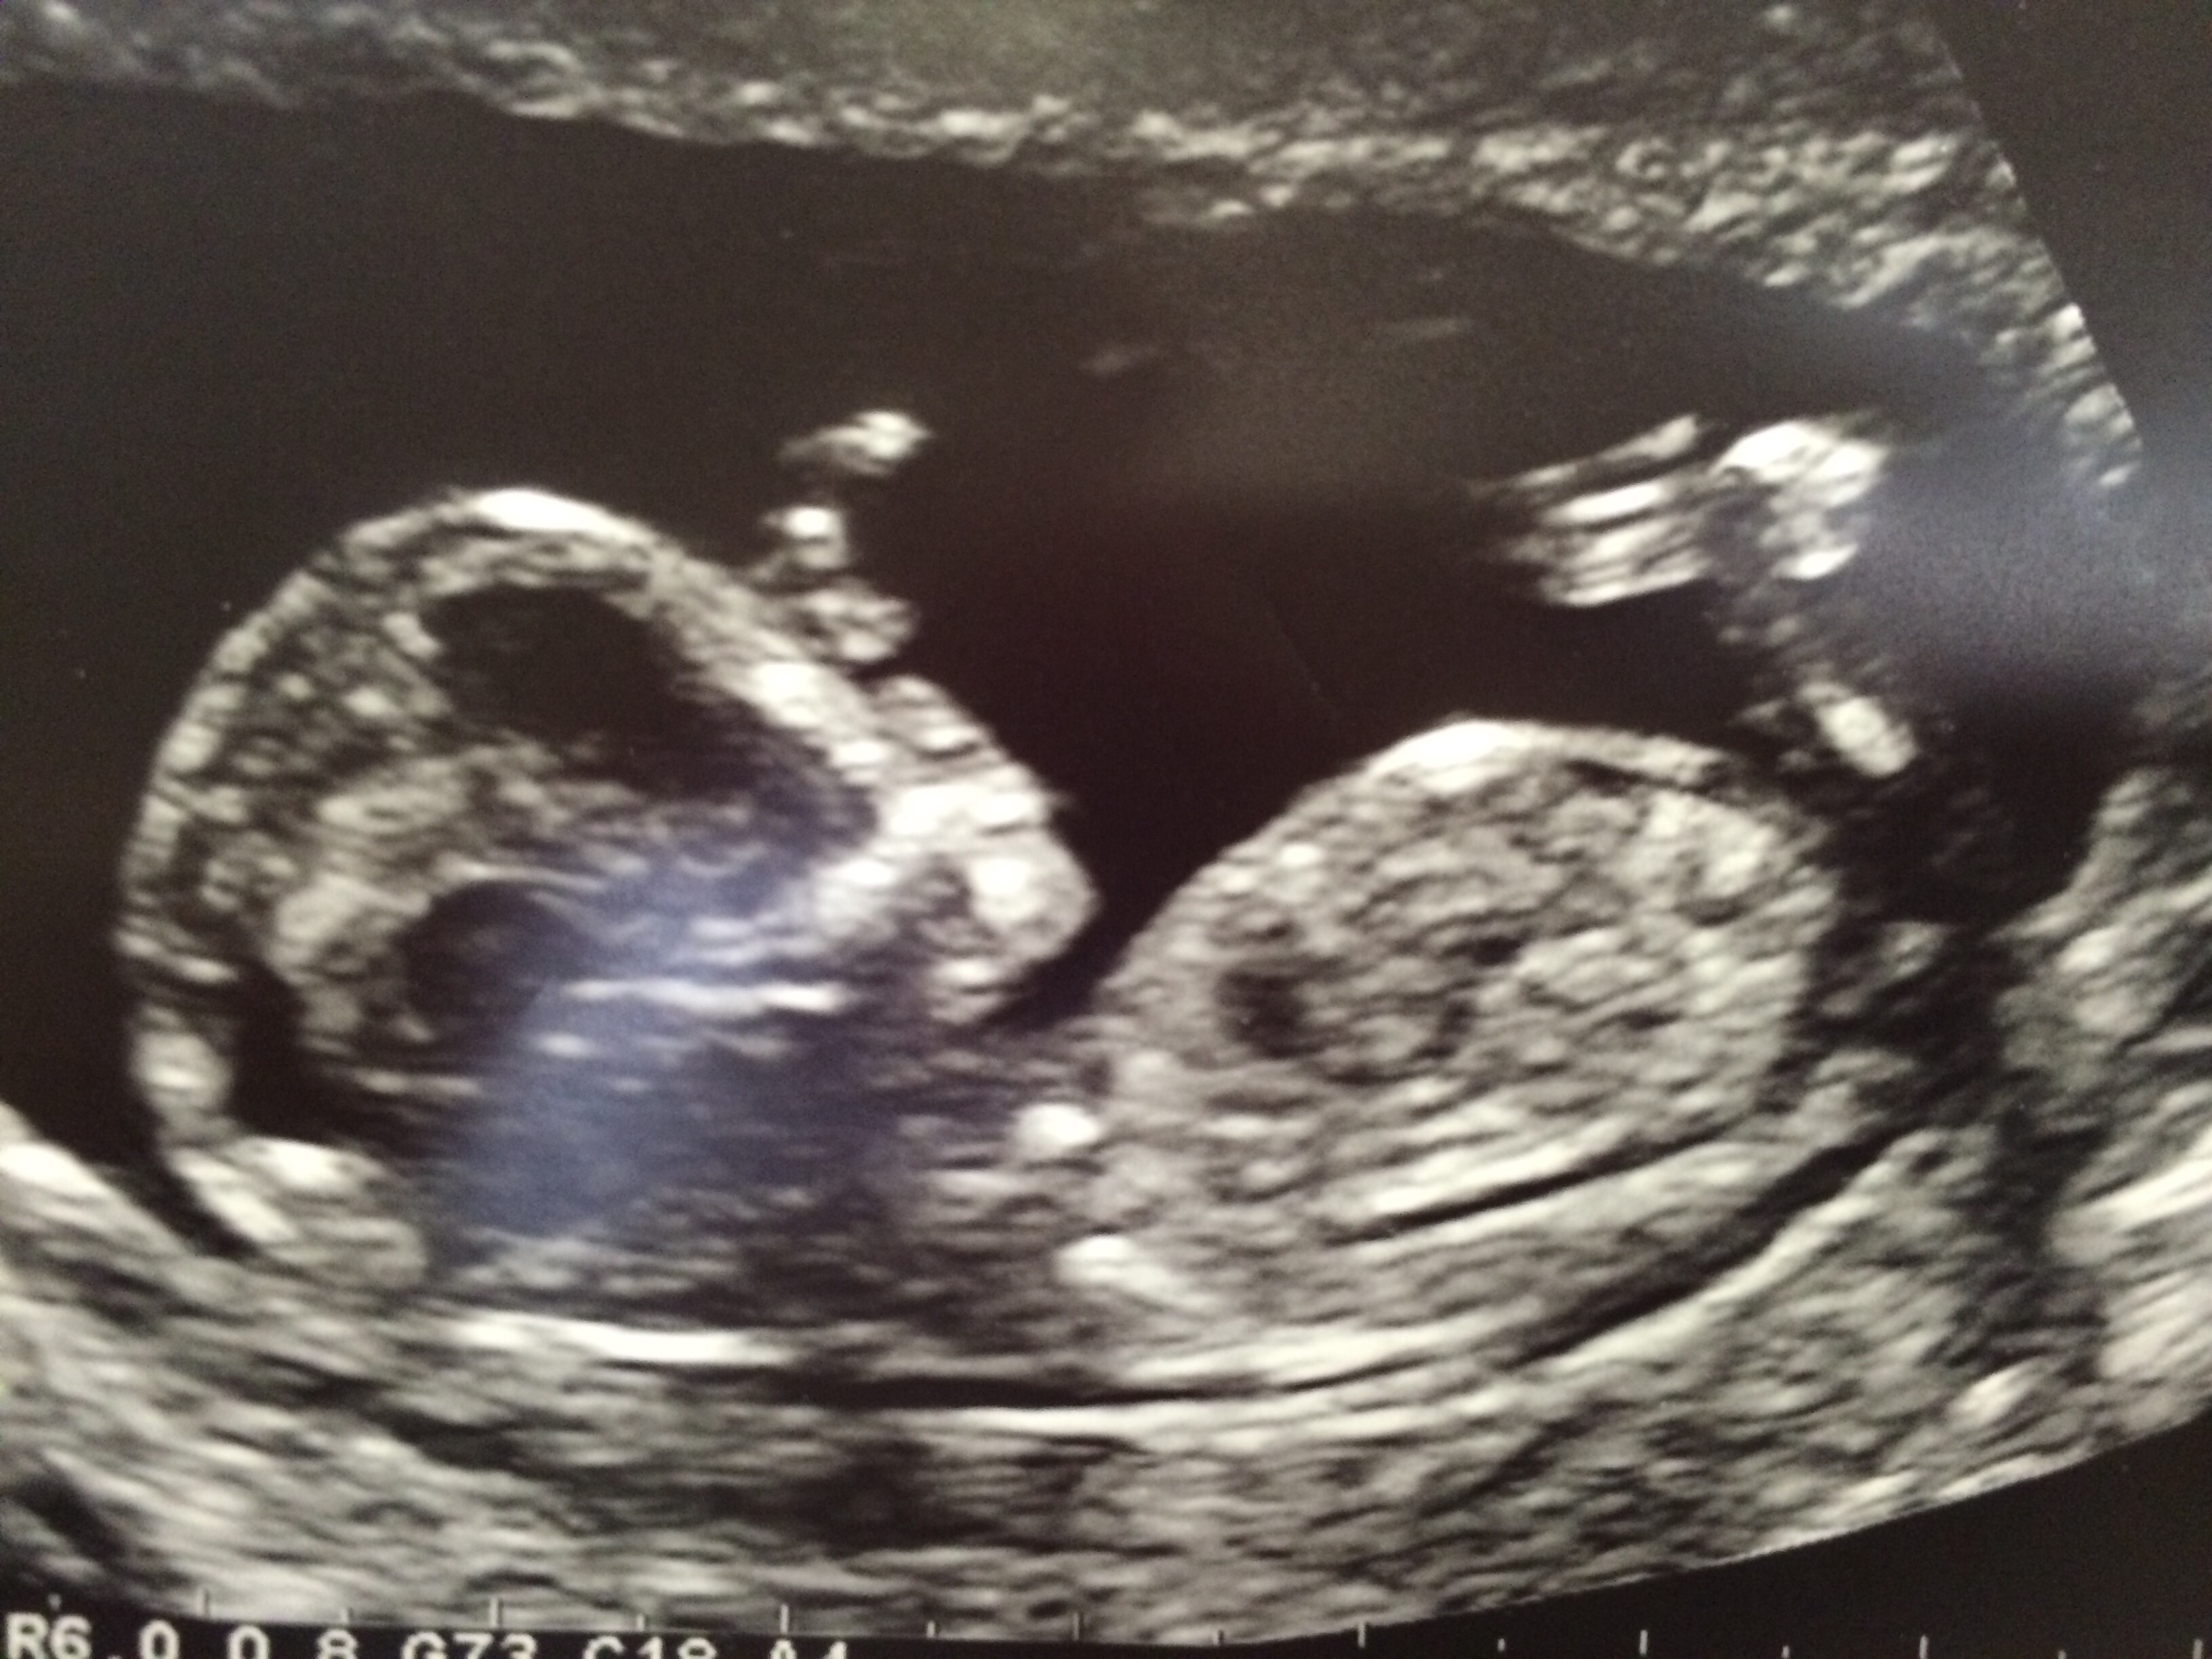

These were taken 13 weeks exactly.

Tricky because of baby's positioning but I would give tentative boy lean from second pic, seems like there is an angle there.

Maybe boy? But not the right angle, babe is turned towards us.

I don't see a nub but skull looks boyish

Think there is nub in 2nd pic. Xx

This is a boy! X